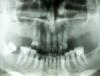

Брат 2 Опубликовано 26 июня, 2013 Поделиться Опубликовано 26 июня, 2013 (изменено) Коллеги интересует Ваше мнение. Глубокий травмирующий прикус, отсутствие жевательных зубов, подвижности практически нет. Принял решение установить по 2 имплантата в боковых участках, прикус вернуть в ортогнатию, оставшиеся зубы депульпировать и шинировать мостовидным протезом. Имеет ли смысл разбивать мост на части? Изменено 26 июня, 2013 пользователем Брат 2 Ссылка на комментарий

Ibulat_1986 Опубликовано 1 июля, 2013 Поделиться Опубликовано 1 июля, 2013 эх жалко на орто суставов не видно. я бы не разбивал на части,каков тогда смысл в шинировании? мне кажется или на нижних фронтальных есть изменения по периапикальным? Ссылка на комментарий

Брат 2 Опубликовано 1 июля, 2013 Автор Поделиться Опубликовано 1 июля, 2013 эх жалко на орто суставов не видно. я бы не разбивал на части,каков тогда смысл в шинировании? мне кажется или на нижних фронтальных есть изменения по периапикальным?Да. Нижними решили заняться позже, по мере фин. поступлений. Даже есть мысли удалить 3.1 , 4.1. Наверху глубокие карманы только на центральных резцах- 3мм, на боковых- 2мм, на клыках- 1мм. Ссылка на комментарий